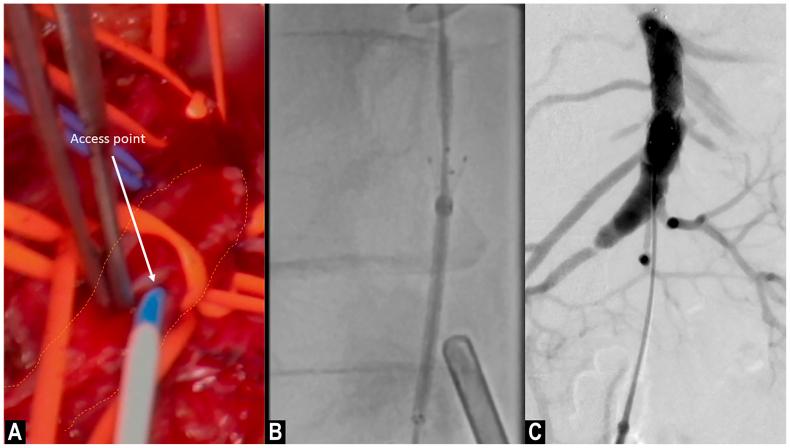

Isolated superior mesenteric artery dissection without aortic involvement is an exceptionally rare event. Nonoperative management remains the first-line therapy. However, surgical interventions can be indicated in the event of bowel ischemia. In the present report, we describe a case of complicated isolated superior mesenteric artery dissection treated with a hybrid approach.

孤立性肠系膜上动脉夹层且无主动脉受累是一种极其罕见的情况。非手术治疗仍然是一线治疗方法。然而,在出现肠缺血的情况下可能需要进行手术干预。在本报告中,我们描述了一例采用杂交手术方法治疗的复杂性孤立性肠系膜上动脉夹层病例。